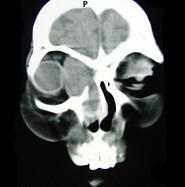

问题 女性,40岁,右眼反复溢泪伴眼球渐进性突出2年余,眼球运动受限,CT检查如图所示,请选择最可能 ( )

选项 A、泪囊血肿 B、眶内结核 C、泪囊囊肿 D、泪腺血肿 E、泪腺囊肿

答案 C